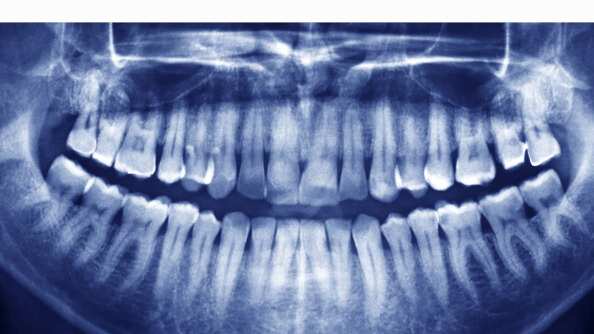

Los exámenes revelaron que tenía un tabique desviado. Además, había algún tipo de obstrucción ósea y un desgarro de dos centímetros de largo en la parte posterior del tabique.

Al usar un rinoscopio, los especialistas encontraron una “masa blanca dura, no dolorosa”, la cual sobresalía del piso de la fosa nasal.

Y al efectuar una tomografía computarizada, dieron con la razón: un diente crecía en un zona en la cual nunca debió haber estado.

El hombre tenía un diente ectópico, término utilizado para la colocación anormal de una parte del cuerpo, de acuerdo a la publicación.